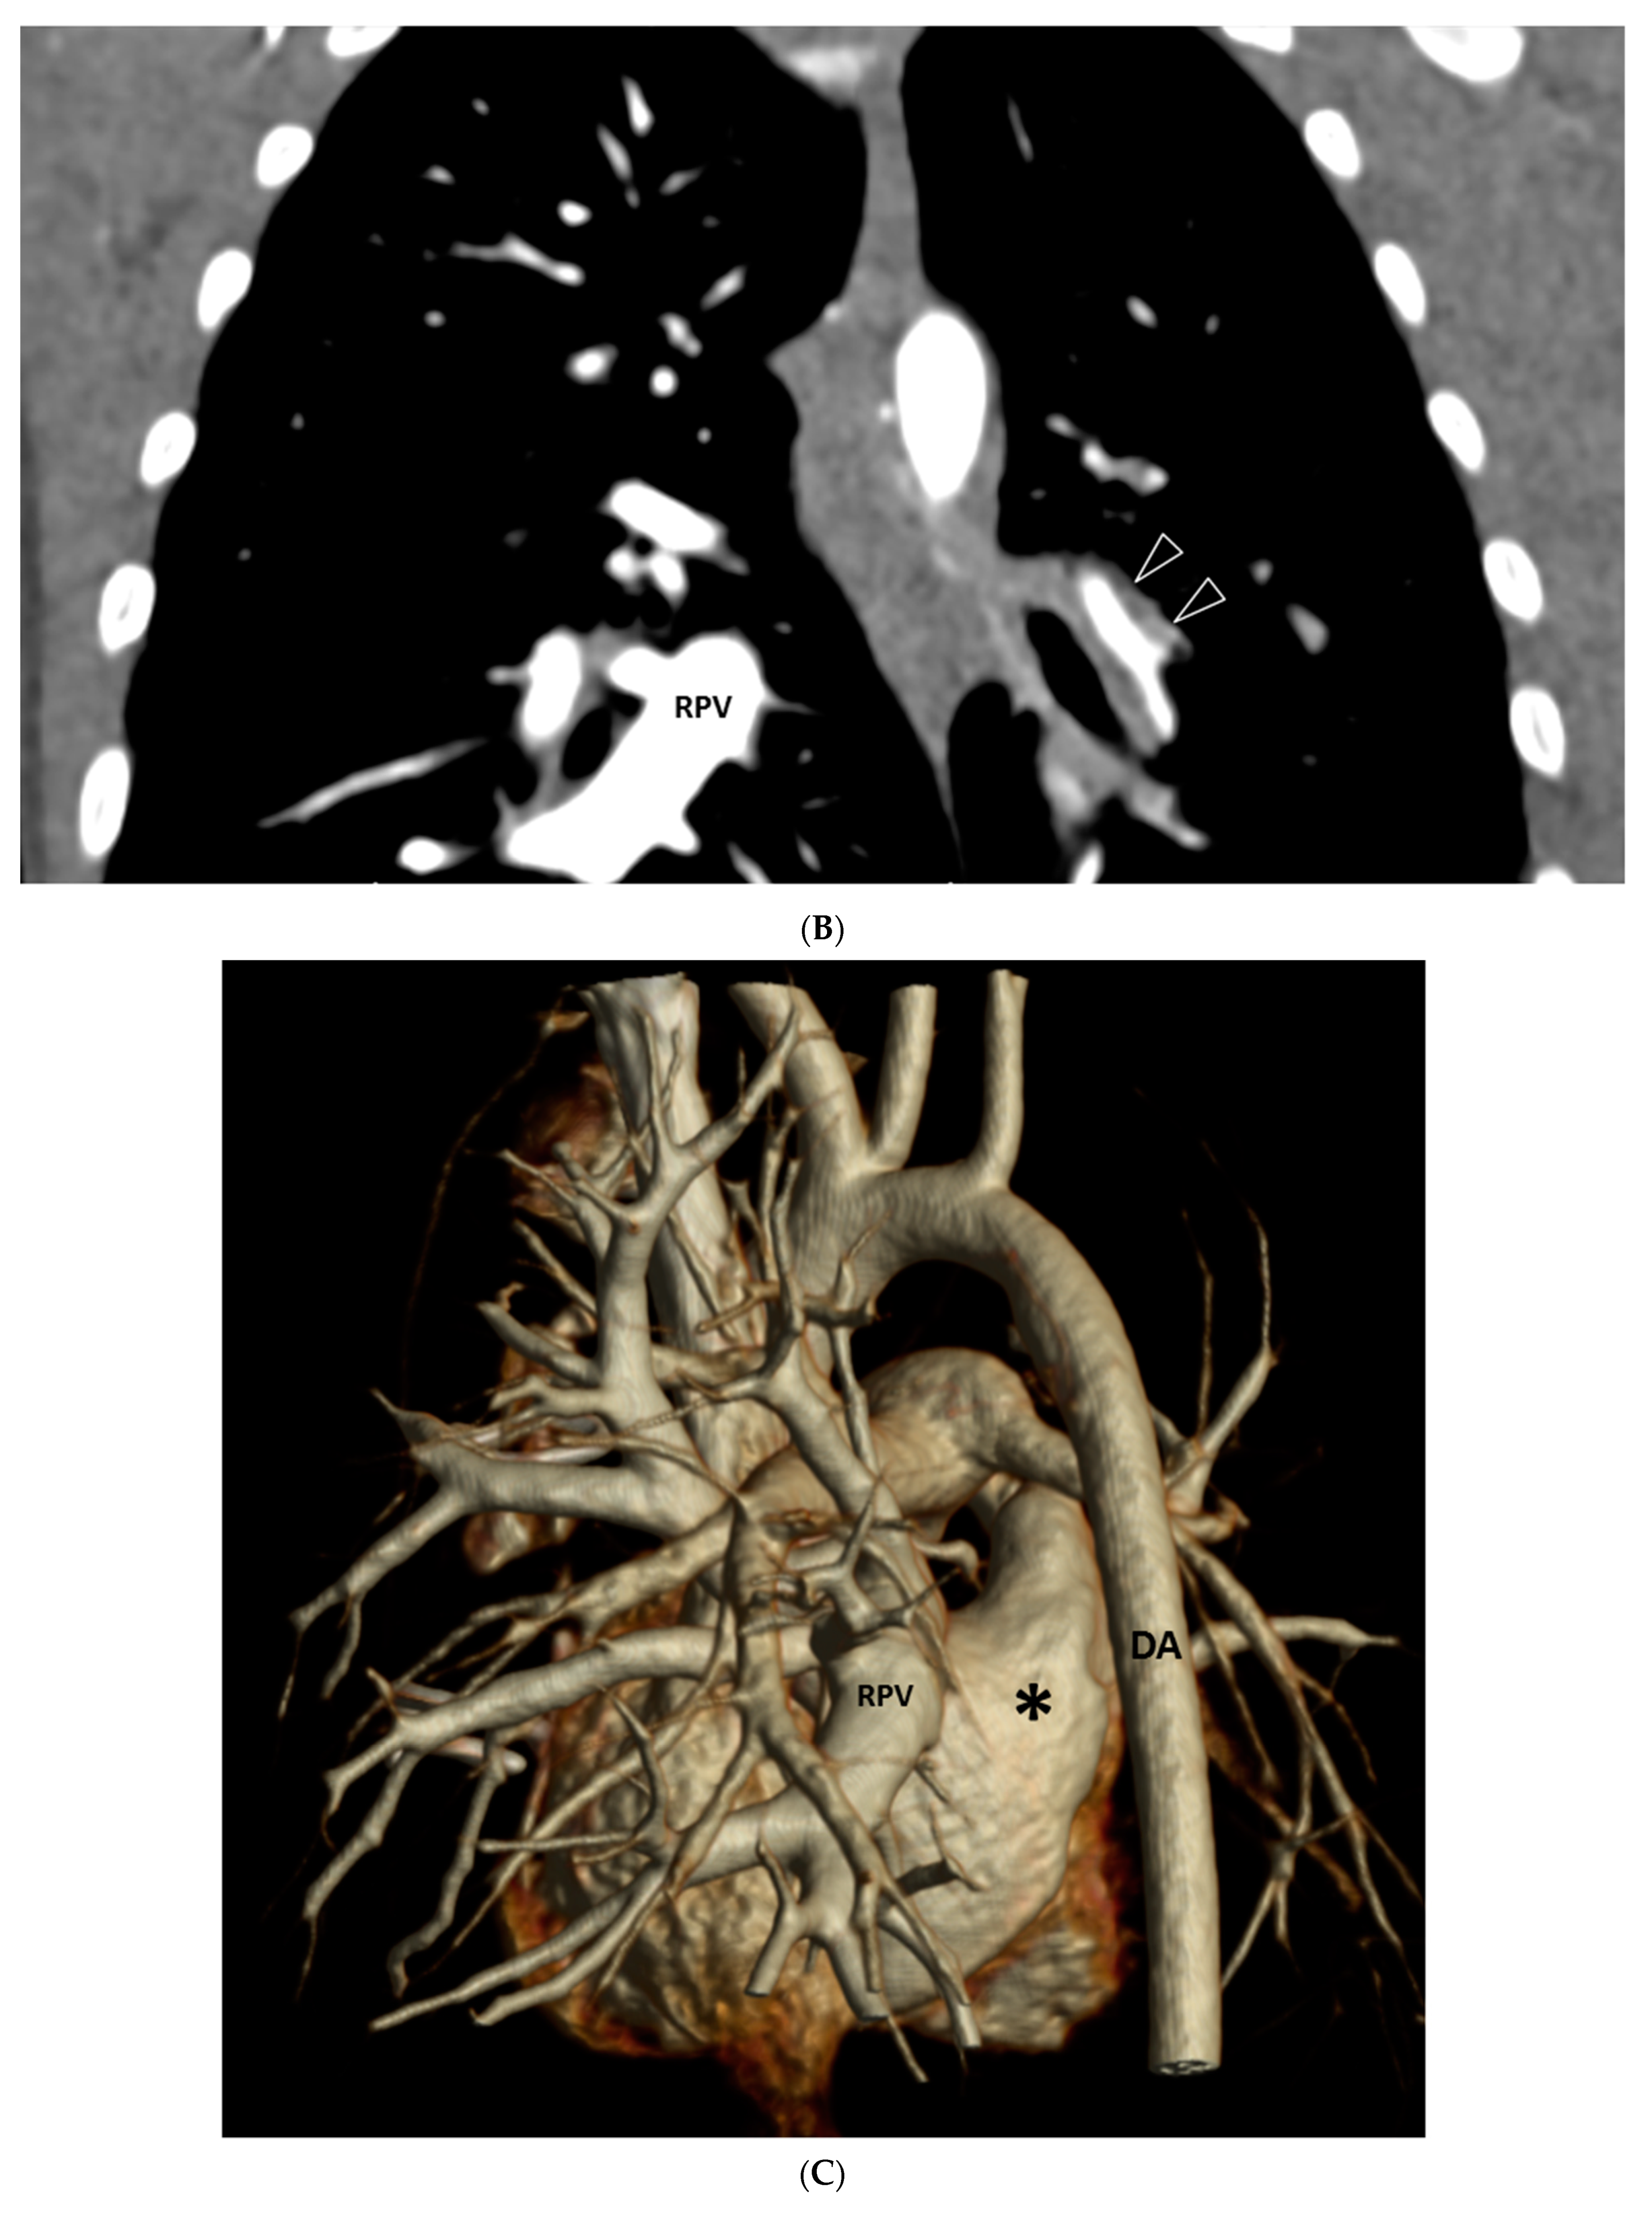

| GGO | 19/20 (95%) |

| Septal Thickening | 7/20 (35%) |

| Pleural Thickening | 17/20 (85%) |

| Mediastinal Mass | 17/20 (85%) |